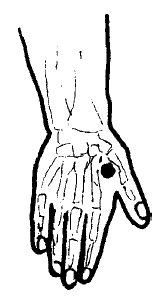

Нередко на коже появляются депигментированные участки — витилиго, а кожа стоп и ладоней может приобрести желто-оранжевый цвет.

Грубые, шершавые локти и пятки, которые многие безуспешно трут пемзой и пытаются смягчить кремами, — тоже признак гипотиреоза на почве йододефицита.